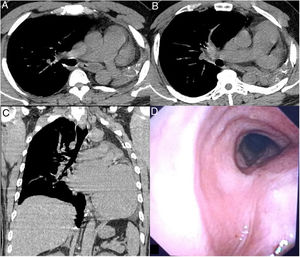

A 40-year-old Chinese man with no significant medical history was admitted to the emergency room with viral gastroenteritis. Physical examination revealed no significant findings, except for the absence of vesicular murmur in the left lung field. Chest X-ray showed left mediastinal shift with left hemitorax opacification. A chest CT was requested, which confirmed left mediastinal shift due to the absence of the left lung and revealed a normal-sized main pulmonary artery with a hypoplastic left pulmonary artery (Fig. 1A-C). Bronchoscopy showed left main bronchial agenesis with mild infundibulum at the supposed anatomical site, with normal mucosa at the carina (Fig.1D). Our patient had pulmonary agenesis that could be classified as type 2, characterized by rudimentary or absent bronchi with complete absence of pulmonary parenchyma. In this rare anatomical defect, one of the main bronchi is replaced by a blind pouch. The left side is the most frequently affected, leading to postpartum compensatory pulmonary herniation toward the left hemitorax1,2. When the malformation occurs in isolation, it is sometimes diagnosed incidentally in adulthood, as occurred in our case.